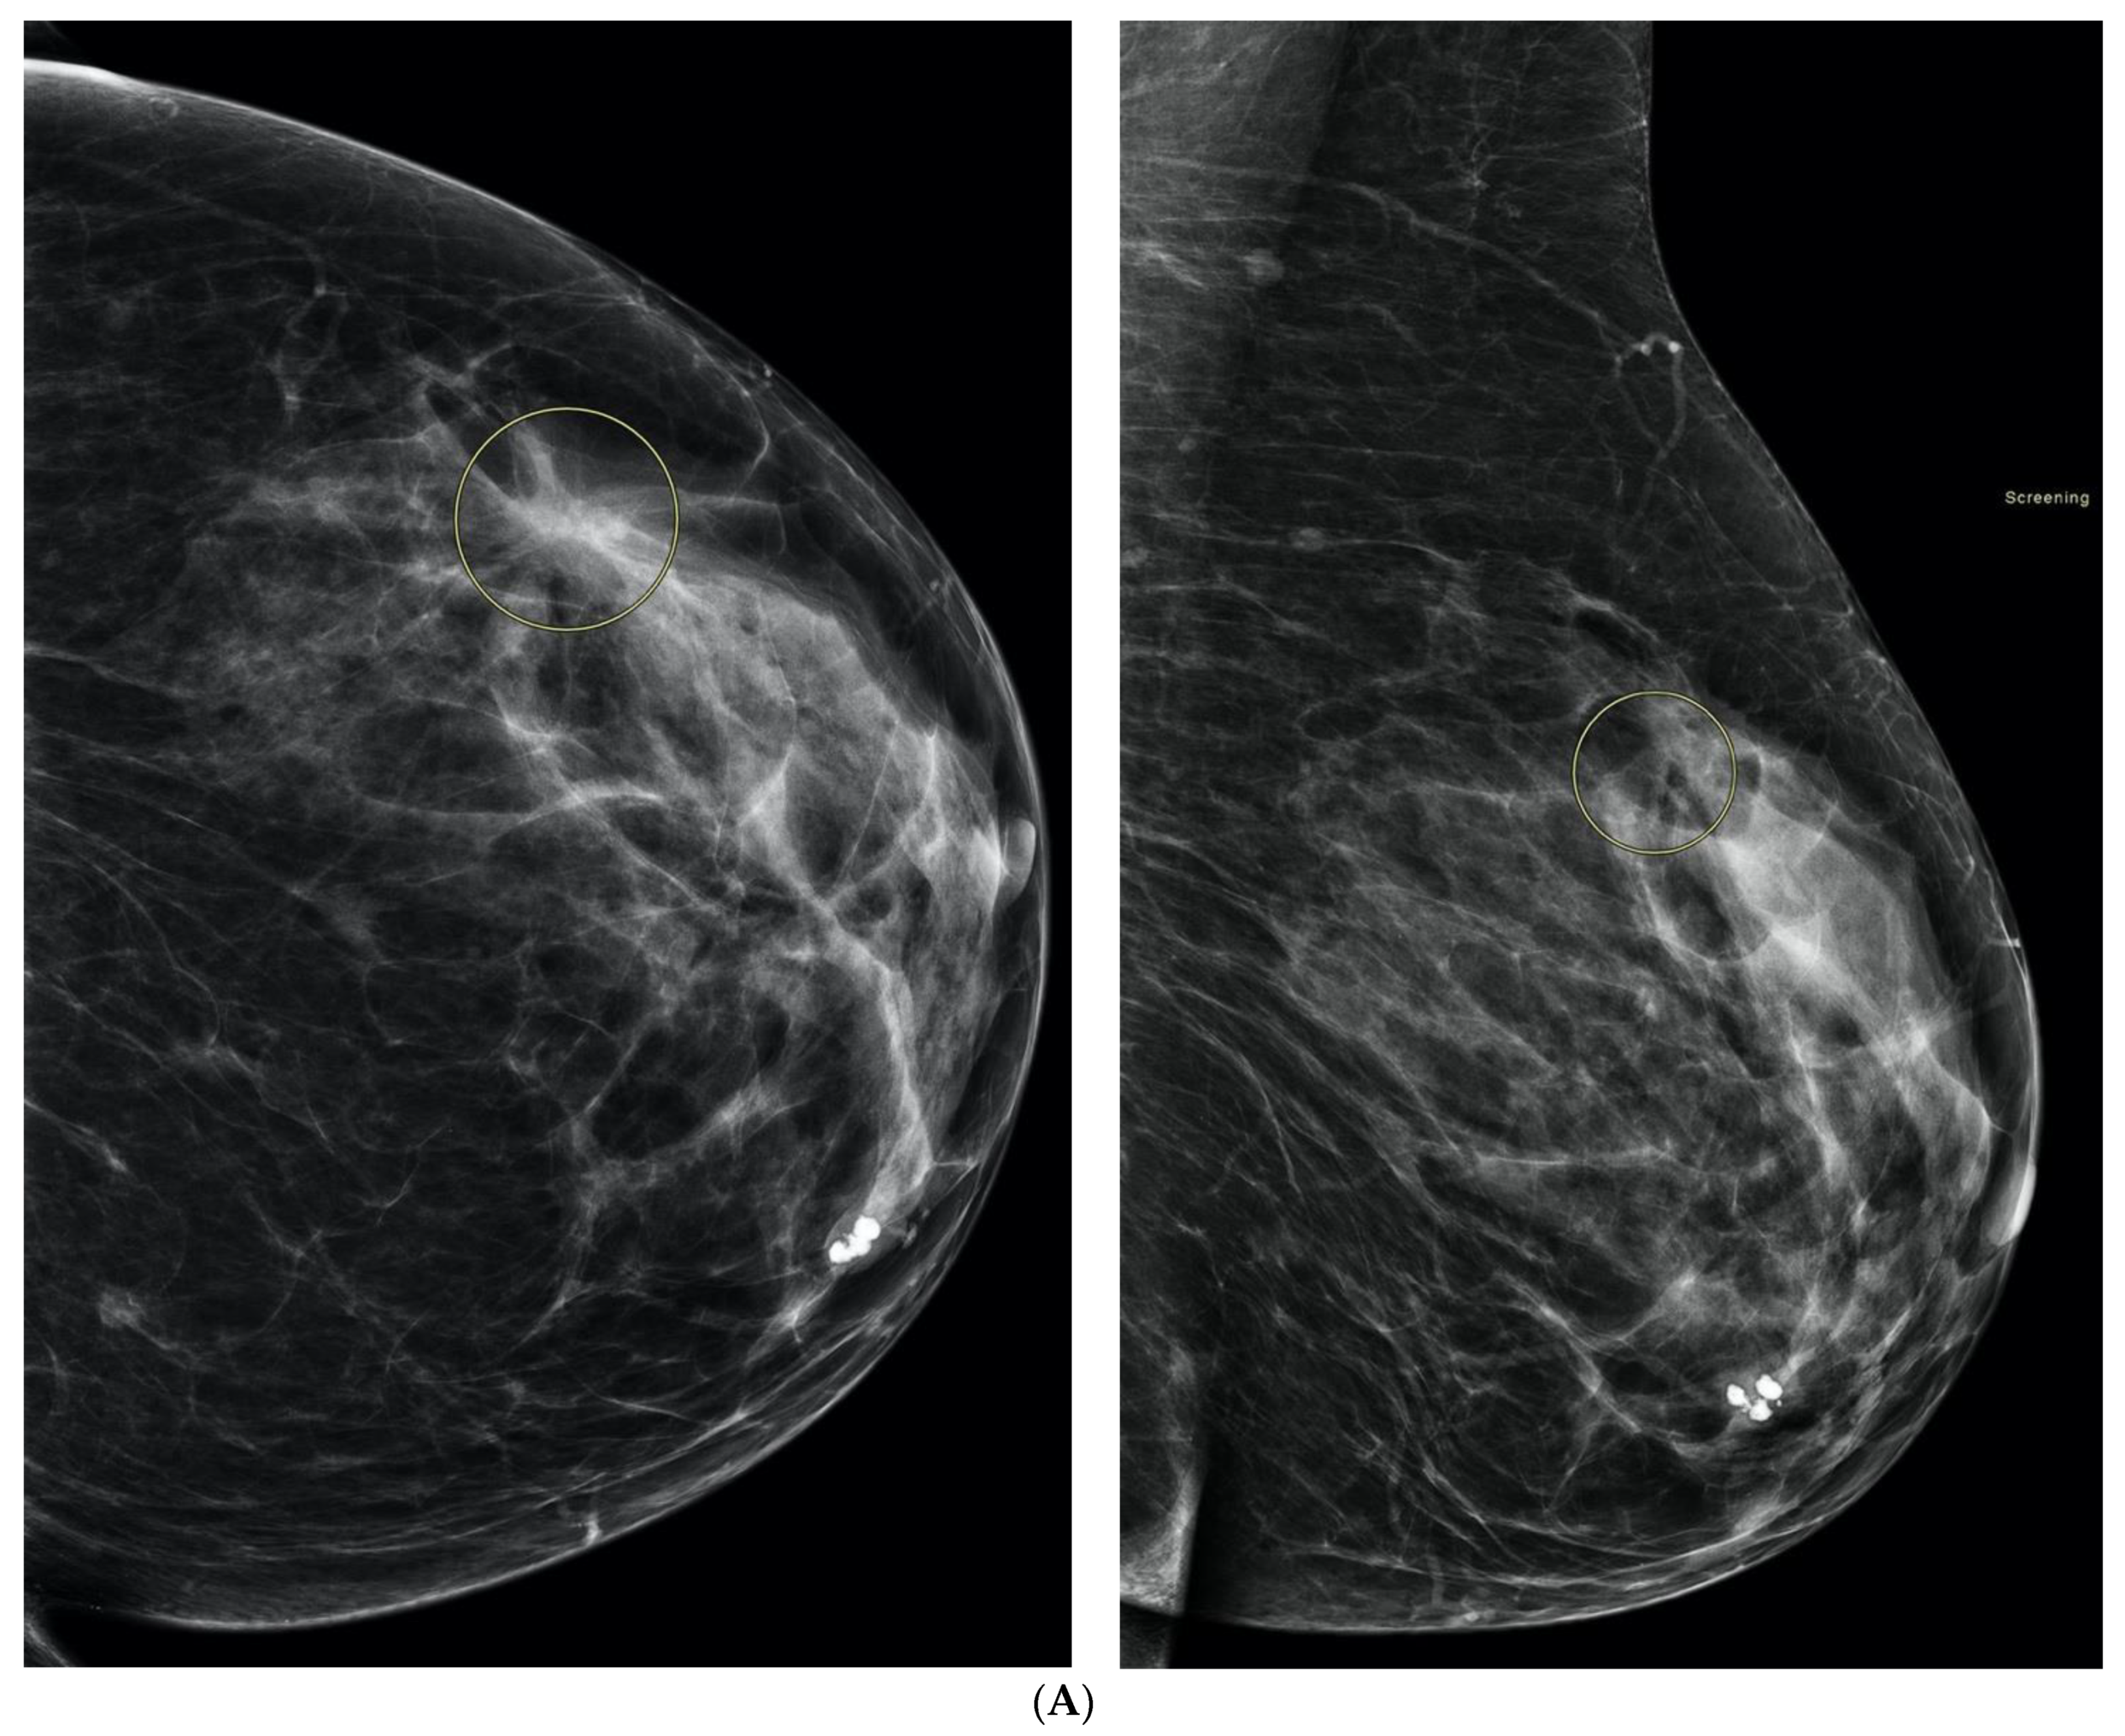

6. Digital Breast Tomosynthesis (DBT)